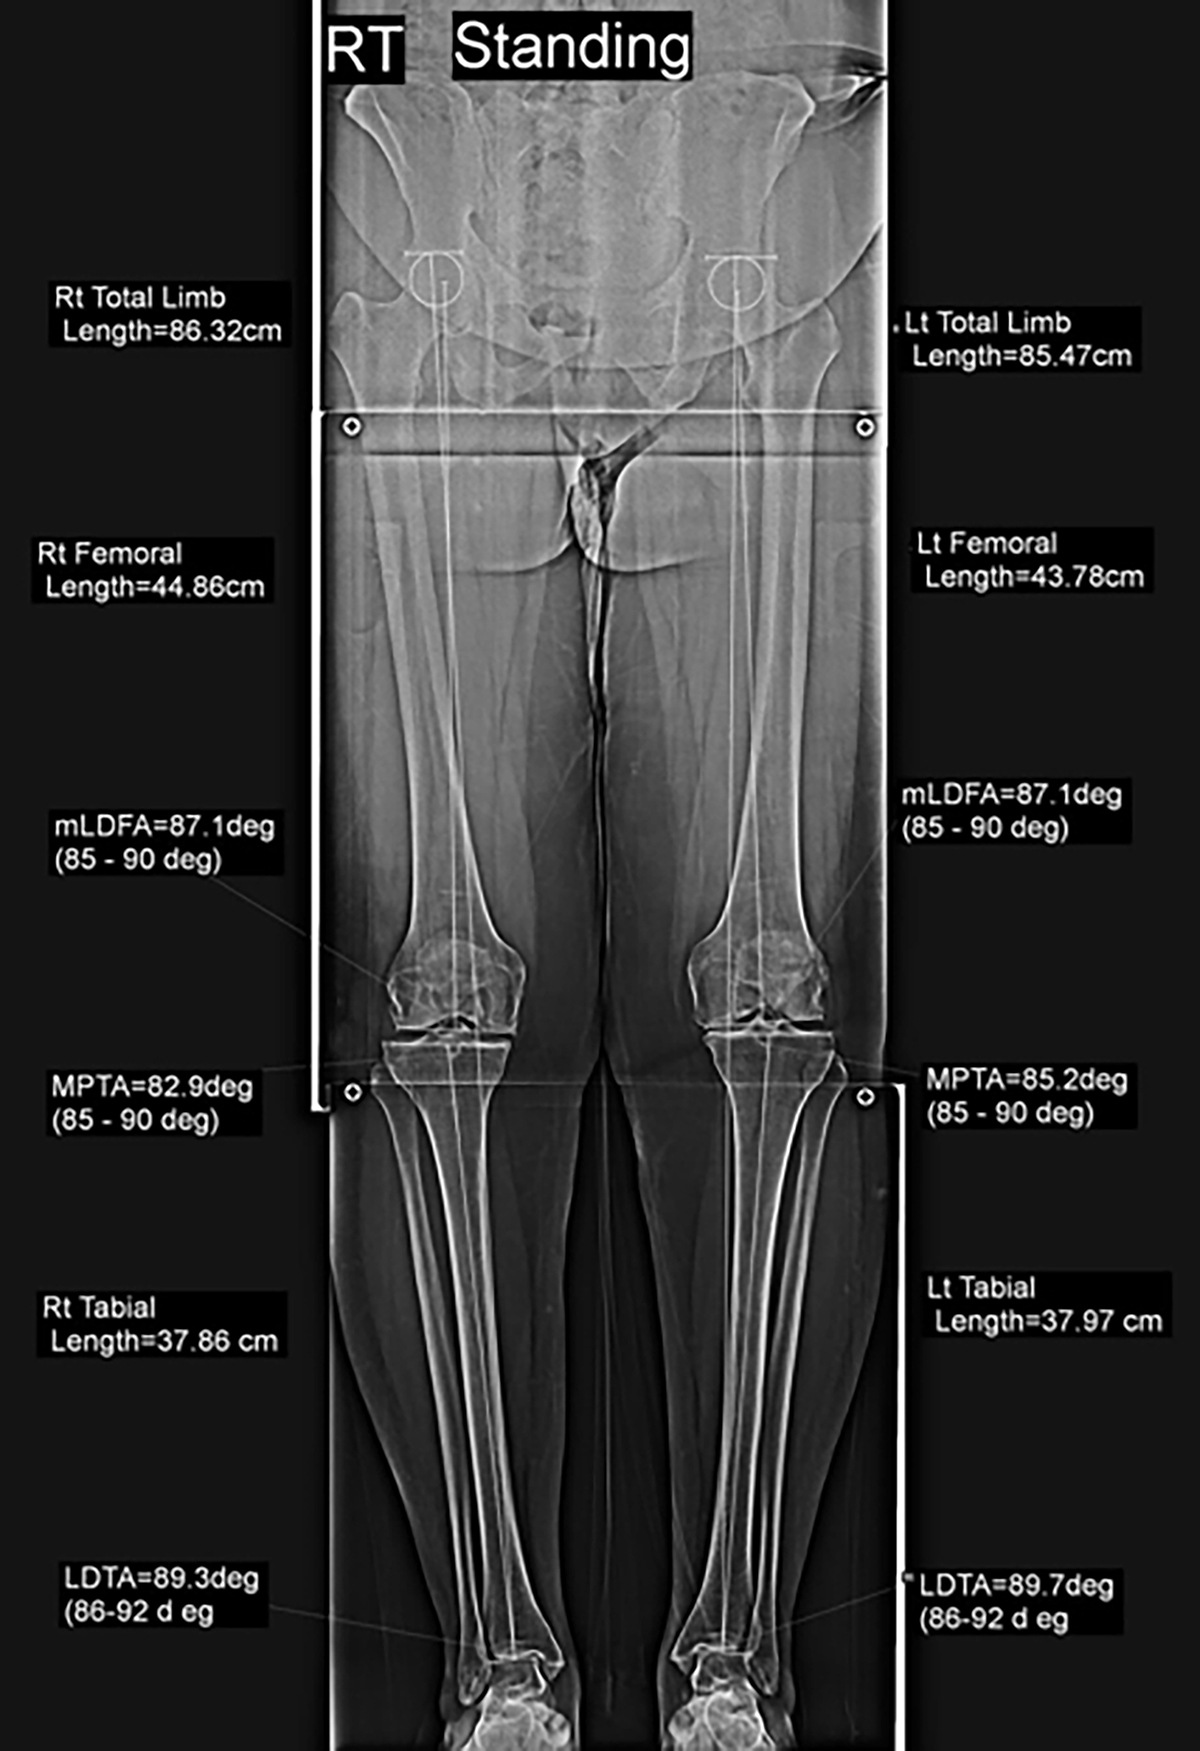

Preoperative planning using standing whole lower limb radiograph.